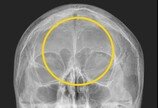

“기생충? 전기칩?”…60대 여성 머릿속 ‘이것’의 정체60대 한국여성의 머릿속에서 기생충처럼 보이는 이물질이 흩어져 있는 엑스레이 사진이 공개돼 화제다.의사이자 작가로 활동하고 있는 가정의학과 전문의 양성관 씨는 최근 자신의 SNS에 ‘한국형 진료’라는 제목의 글과 사진을 올렸다.양 씨는 “엑스레이에서 1cm 크기의 다수의 이물질이 발견…2025-03-13 06:00:00